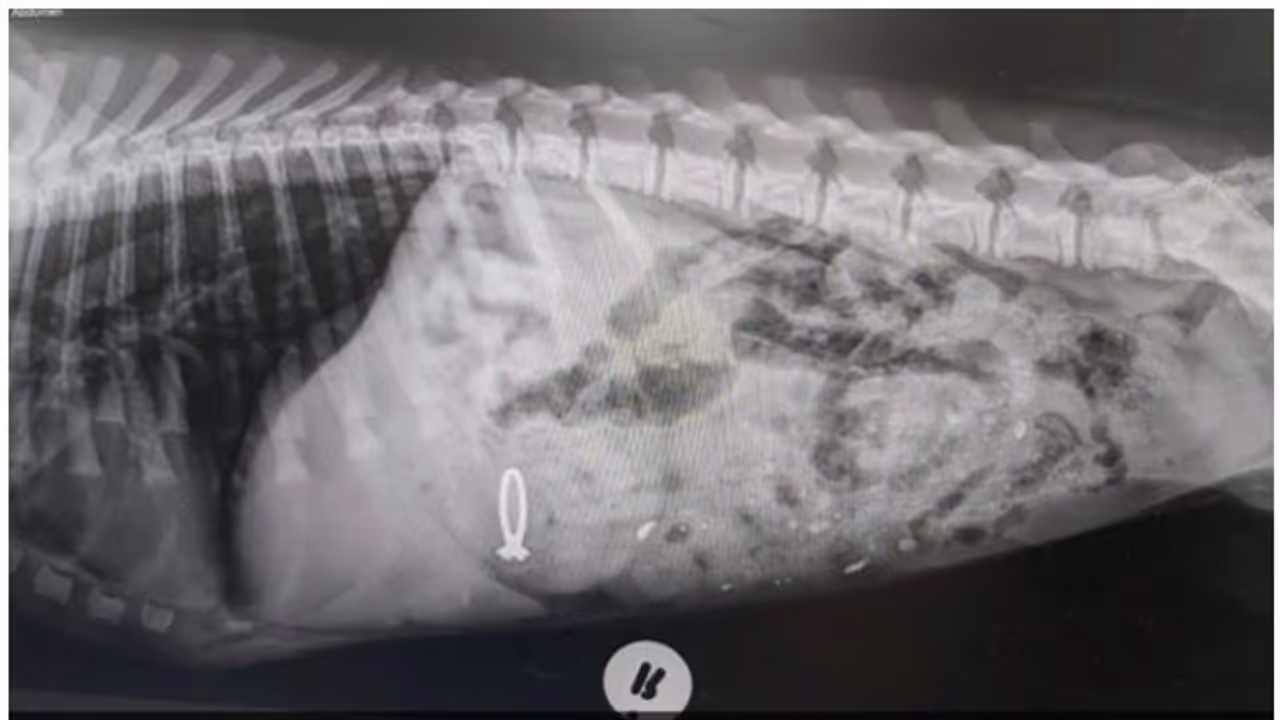

കൂടുതലൊന്നും ചോദിക്കരുത്. ഇതൊരു നല്ല ആശയമാണെന്ന് കരുതിയാണ് പങ്ക് വയ്ക്കുന്നതെന്നും കുറിപ്പിൽ പറയുന്നു. ഒപ്പമുള്ള ചിത്രത്തിൽ പെപ്പറിന്റെ വയറിനുള്ളിലെ എക്സേറയുമുണ്ട്. വിഴുങ്ങിയ വിവാഹമോതിരം സുരക്ഷിതമായി തന്നെ അവന്റെ വയറ്റിലുണ്ടെന്ന് എക്സ്റേയിൽ നിന്ന് വ്യക്തമാണ്. അവസാനം പെപ്പറിനെ ഛർദ്ദിപ്പിച്ച് മൃഗഡോക്ടർമാർ മോതിരം തിരികെയെടുത്തും. ഉടമയ്ക്ക് തിരിച്ചു കൊടുക്കുകയും ചെയ്തു.